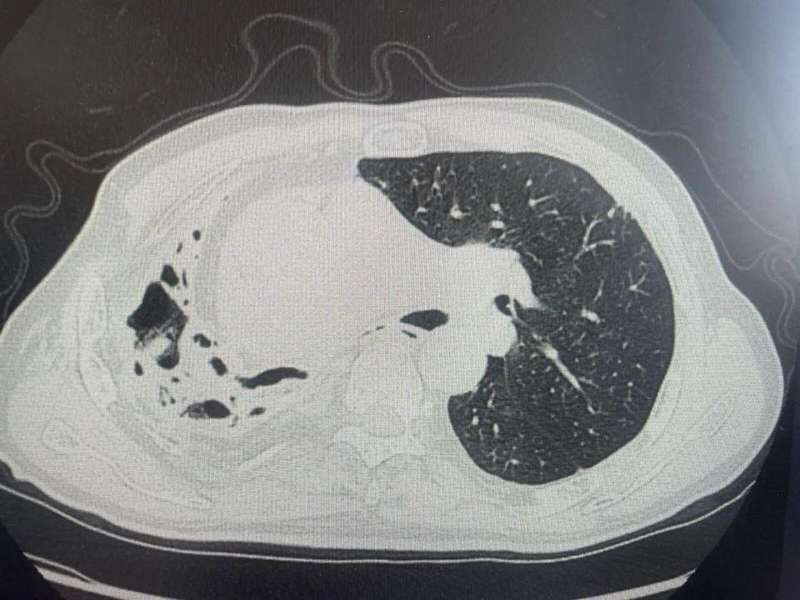

杭州富阳一位七十岁的王大伯,年轻时有过肺部相关病史,近期在山林中频繁活动后,突然出现反复咯血的情况。家人最初判断为旧病反复,但医院的CT检查结果显示,他的右肺已发生显著结构改变,呈现蜂窝状外观,功能也受到明显影响。这一发现让医疗团队迅速展开深入调查,以找出背后的真正原因。

经过支气管镜检查和先进测序技术,医生确认了感染源头是一种在自然环境中常见的真菌。它在我国南方及周边地区分布较广,主要与竹林生态系统相关。这种条件致病菌的孢子常常隐藏在土壤、枯枝落叶之中,当人体在劳作时吸入后,可能在肺部引发深部感染。初期症状包括咳嗽、胸痛等,与多种呼吸系统疾病表现相似,影像学特征也不够典型,因此容易出现诊断上的延误。

流行病学调查显示,王大伯的活动轨迹与感染密切相关。他近期多次进山挖笋,在翻动土壤和接触植被的过程中,无意中吸入了混杂其中的真菌孢子。这类真菌以竹鼠为主要宿主,在竹林环境中较为活跃。对于有基础肺部问题的个体,感染后可能导致肺组织严重受损。幸运的是,经过规范的抗真菌治疗,老人病情逐渐平稳,目前正在呼吸专科门诊进行定期随访,以观察肺部恢复进展。